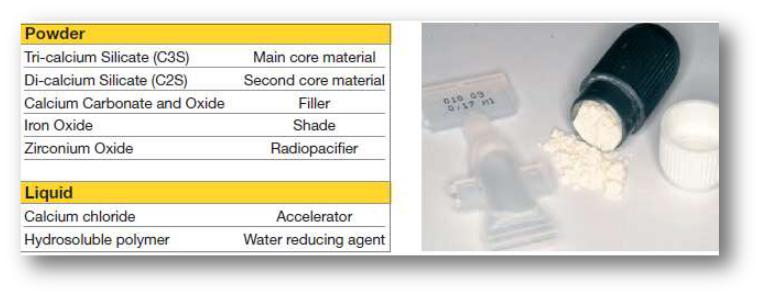

МТА – минеральный триоксидный агрегат

•Смесь соединений кальция (трикальцийсиликат), железа и алюминия, гидратированного сульфата кальция и гипса.

•Оксид висмута – для R контрастности

Высокая степень биологической совместимости Активирует цементогенез Активирует дентингенез

Обеспечивает апикальную герметизацию

Минеральный триоксид кальция ProRoot MTA (Dentsply)

Происходит его прочное сцепление с твердыми тканями во влажных условиях.

.При увлажнении порошок превращается

в гель, который застывает и создает непроницаемый барьер. Он обеспечивает формирование

дентинного мостика

или нового цемента при закрытии перфорации корня.

Материалы, содержащие МТА

Pro Root

Триоксидент

MTA-Angelus

Радоцем

биодентин

Biodentine™